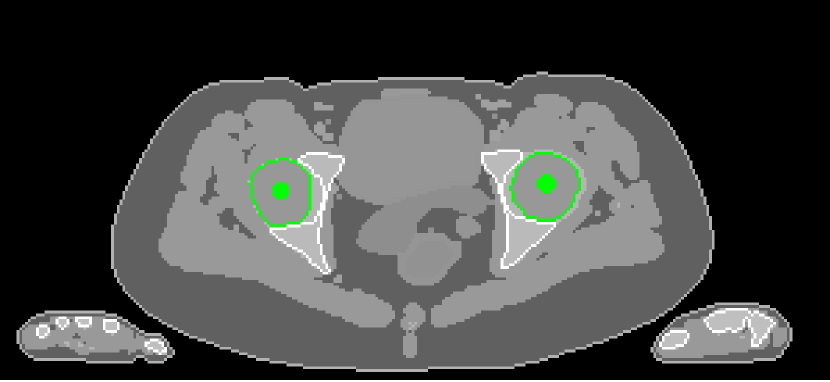

4.2 Low Dose Numerical Reconstruction Test

The data we used for our numerical reconstruction test were derived from the Adult Reference Computational Phantom (ICRP Publication 110,, 2009), which is a segmented image of defined density and chemical composition to represent real tissues. To investigate the ability to image metal implants, we inserted a pair of prosthetic hip joints (marked in green) with a solid titanium pin and shell. The slices through the chest and pelvis—which are the images we selected for testing—are shown in Figure 8. The resolution is 299×137299137299\times 137.

Refer to caption

(b) Pelvis test image

Figure 8: Experimental data used: (a) is the oracle chest electron density; and (b) is the oracle pelvis electron density; both have a with display window of [0.8,1.2]

• Poly-SIR: Polyenergetic statistical iterative reconstruction (Poly-SIR) is the segmented water–bone model from (9) (Elbakri and Fessler,, 2002). As this requires prior knowledge on material classes, we give it the oracle segmentation of the hard bone structures, and it treats everything else as water. In the pelvis case, we also pass the oracle segmentation of the metal implants, with corresponding mass attenuation coefficients. Since the physical model gives the mass density, we convert to relative electron density where appropriate using the curve shown in Figure 2(b).

• Polyquant: In our proposed model, we use the piece-wise linear fitting in Section 3.1 and reconstruction strategy in Section 3.2. We use Algorithm 1, but with 10δ10𝛿10\delta which from Figure 4 is still rather conservative, but still exhibited a monotonic decrease in the objective function. For the pelvis case, we extend the model with a second ‘knee’ point and linear section to include the attenuation of solid titanium according to the generalisation in (10). We used separate fittings to electron and mass density shown in top and middle graphs in Figure 3, to demonstrate the ability to reconstruct directly into either quantity, where each mapping was a least-squares fitting to the materials in ICRP 89 (ICRP Publication 89,, 2002).

The results from our reconstruction test are illustrated in Figure 9 and Table 3.

Figure 9: Results from electron density reconstruction test for chest and pelvis fan-beam data with display window [0.8,1.2] to aid visualisation of soft tissue and reconstruction artefacts

In terms of both electron density and mass density accuracy, our proposed method is the best performing method under test. The lack in estimation accuracy in using the water–bone model with Poly-SIR is likely to be due to discrepancies in adipose and spongy bone tissues from water, which were illustrated in Figure 5. We note that Poly-SIR is second best performing in the pelvis case, but it was provided with oracle information on the implant and hard bone, which would be difficult to segment in practice from a preliminary reconstruction such as FBP due to its high noise. IMPACT is understandably very closely performing to our method in the chest case, as these performed similarly in the model test, but the advantage of fitting at each energy is clear in the case of the metal implant, where the IMPACT performance is similar to that of PWLS.